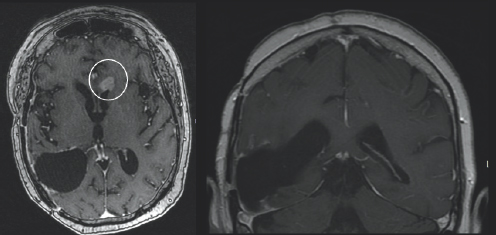

(Left) There is charcoal grey color surrounded by black space and a thin light grey outline. On the left side of the image, there is a black blob with two small white blobs beneath it which are highlighted by two small white arrows. (Right) There is charcoal grey color surrounded by black space and a thin light grey outline. On the left side of the image, there is a black blob with a white spherical figure above it with is highlighted by a small white arrow.

FIGURE 3.2 Brain MRI after surgery. Axial (right) and coronal (left) post-contrast images show postoperative changes from resection of the mass. Follow-up post-contrast images, obtained 29 months follow-up, demonstrate new nodular areas of abnormal enhancement that appear bright after being injected with IV contrast, along the superior and anterolateral margins of the resection cavity (white arrows), concerning for recurrent tumor.

A month after her surgery, Janet began chemotherapy and radiation treatment. She began trialing different chemotherapy drugs recommended by her team of physicians to pinpoint which would be most effective for her tumor. She was unable to be treated with the standard-of-care drug, TMZ, due to a severe anaphylactic allergic reaction. Despite desensitization to try to ween her on TMZ use, she continued treatment with lomustine, a different chemotherapy drug. Janet was placed on multiple clinical trials starting with the Belinostat/MRSI (magnetic resonance spectroscopic imaging) study and later the 5-ALA (5-aminolevulinic acid) study. Early on in her treatment, Janet turned to tumor treating fields (TTFs), to see if that form of treatment could provide her the benefit of tumor reduction. TTFs are commonly used in the form of an Optune® device. An Optune® device is a physical, white-colored cap that patients can place over their shaved heads to reduce cancer cell growth through the electric fields that the device omits. In the fall of 2019, Janet moved her care from Emory University Hospital and Wake Forest Hospital to the University of Cincinnati Medical Center to follow her neuro-oncologist, Dr. Soma Sengupta, with whom she had formed a close relationship. Due to the progression of her disease Janet underwent a re-resection surgery in March of 2020 and was placed on the adjuvant letrozole drug study. She then started the chemotherapy drug bevacizumab and required stereotactic radiosurgery (SRS) for a new lesion (Fig. 3.2–3.4). She continued care through her doctors in Cincinnati in conjunction with the care she was receiving at Wake Forest Hospital. She felt prepared but nervous each time she underwent imaging because she knew if her tumor had grown, it would result in a change of course to her treatment.